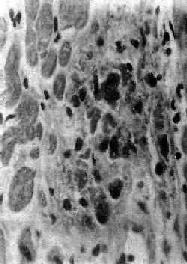

图8-19 Aschoff小体 主由Anitschkow细胞、Aschoff巨细胞和淋巴细胞等组成,中心部常有纤维素样坏死物 3.瘢痕期(愈合期) 细胞成分减少,出现纤维母细胞,产生胶原纤维,并变为纤维细胞。整个小体变为梭形小瘢痕。此期经过约2~3个月。 本病病变的自然经过为4~6个月,但常反复发作,因此,新旧病变常同时并存。 发生在浆膜的风湿病变主要为浆液性和(或)纤维素性炎症。

| 二、基本病变风湿热时,病变可累及全身结缔组织,特别是心脏各层均可被累及;小动脉亦往往被侵犯。病变发展过程大致可分为三期: 1.变质渗出期 开始是结缔组织纤维发生粘液样变性,可见胶原纤维肿胀(原纤维间水肿,intermicrofibrillary edema),结缔组织基质内蛋白多糖(主要为氨基葡聚糖)增多。HE染色呈嗜碱性,甲苯胺蓝染色呈异染性,即呈红色。继而肿胀的胶原纤维断裂、崩解成无结构的颗粒状物,与基质中的氨基葡聚糖混合在一起,加上免疫球蛋白、有时还有纤维蛋白沉积,致使病灶的染色性状颇似纤维蛋白,因此称为纤维素样变性(纤维素样坏死)。此外,病灶中还有少量浆液和炎症细胞(淋巴细胞、个别中性粒细胞和单核细胞)浸润。此期持续约1个月。 2.增生期 亦称为肉芽肿期(granulomatous phase ),其特点是形成具有疾病特征性的风湿性肉芽肿,即Aschoff小体(Aschoff body),对本病具有诊断意义。 Aschoff 小体体积颇小,一般显微镜下才能看见(图8-19),多发生于心肌间质、心内膜下和皮下结缔组织;心外膜、关节和血管等处少见。在心肌间质内者多位于小血管旁,略带圆形或梭形,其中心部为纤维素样坏死灶,周围有各种细胞成分:①Anitschkow细胞:胞浆丰富,嗜碱性,核大,呈卵圆形、空泡状。染色质集中于核的中央,核的横切面状似枭眼;纵切面上,染色质状如毛虫。②Aschoff巨细胞(Aschoff giant cell):含有1~4个泡状的核,与Anitschkow细胞相似,胞浆嗜碱性。以上两种细胞的来源尚有争论,但现代标记技术证明其为巨噬细胞源性。③小体内还有少量淋巴细胞(主要为T细胞)和个别中性粒细胞。此期经过约2~3个月。